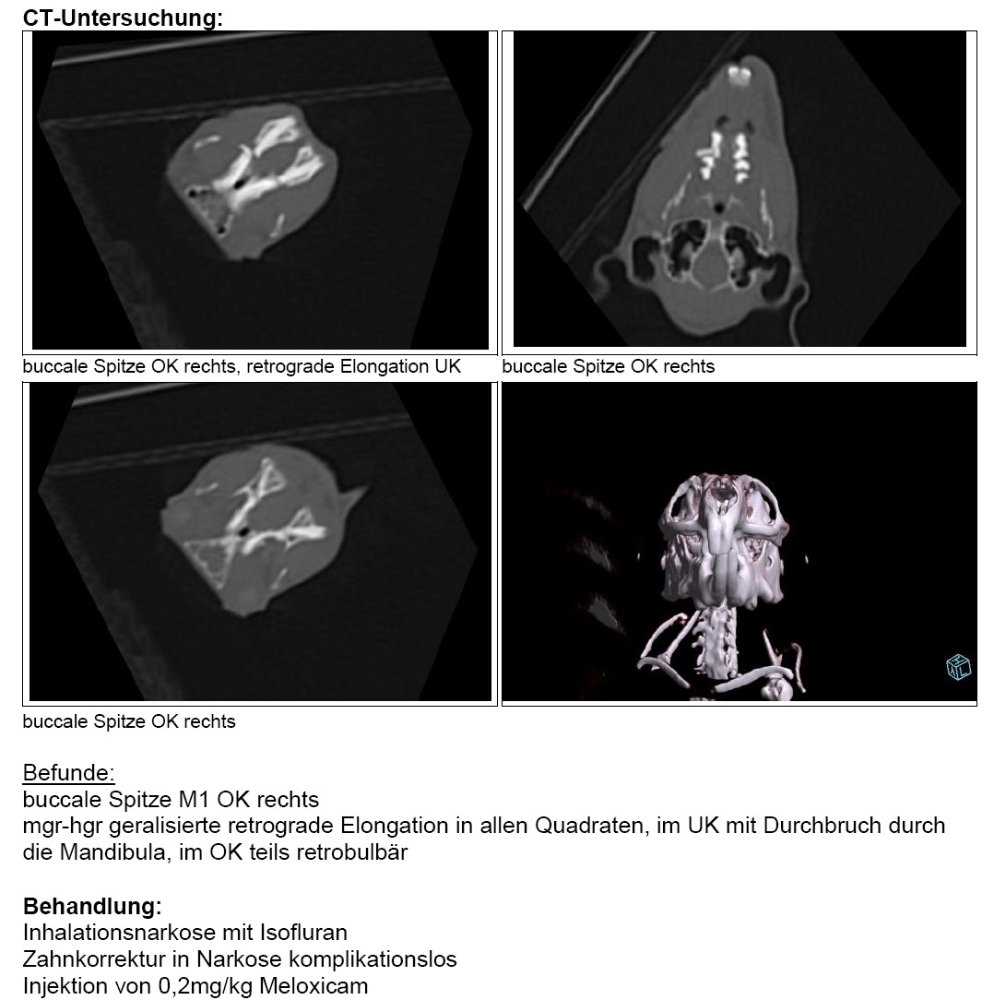

Befunde:

buccale Spitze M1 OK rechts

mgr-hgr geralisierte retrograde Elongation in allen Quadraten, im UK mit Durchbruch durch die Mandibula, im OK teils retrobulbär

Behandlung:

Inhalationsnarkose mit Isofluran Zahnkorrektur in Narkose komplikationslos Injektion von 0,2mg/kg Meloxicam

Zusammenfassung:

Obwohl die Zahnbefunde hochgradig und chronisch sind, tritt dies bei älteren Degus häufig auf, ohne Probleme zu verursachen. Eine kausale Therapie ist nicht möglich.

Die buccale Spitze wurde beseitigt. Da bereits Schleimhautläsionen vorlagen, ist davon auszugehen, dass dies der Grund für das Speicheln und sie Fressproblematik darstellt.

Weitere Behandlung:

Melosus 0,5mg/kg 1xtgl 1 Tropfen ab morgen über 3 Tage

Hier ein Ausschnitt des Befundes für die, die es interessiert *winkend*